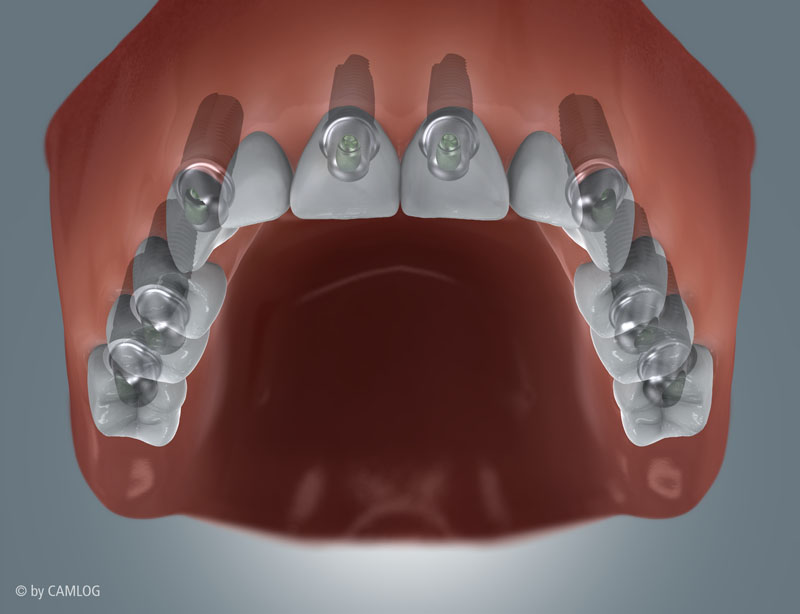

Unterkiefer, fixe Brücke